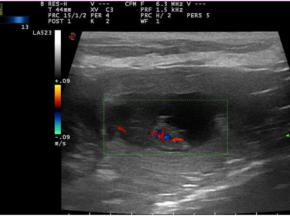

Ich werde Mama, der heutige Ultraschall war positiv.